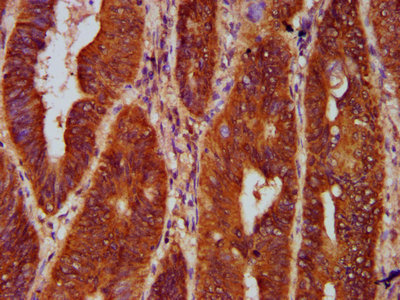

IHC image of CSB-PA009716LA01HU diluted at 1:300 and staining in paraffin-embedded human colon cancer performed on a Leica BondTM system. After dewaxing and hydration, antigen retrieval was mediated by high pressure in a citrate buffer (pH 6.0). Section was blocked with 10% normal goat serum 30min at RT. Then primary antibody (1% BSA) was incubated at 4°C overnight. The primary is detected by a biotinylated secondary antibody and visualized using an HRP conjugated SP system.